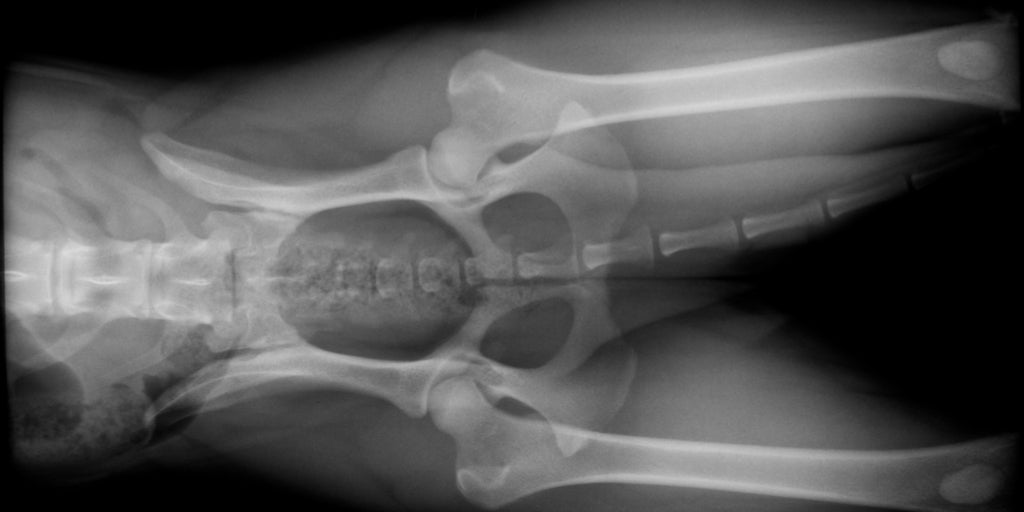

These X-rays are of the same dog. As you can see, the distraction view shows much more laxity in the hips than the standard hip-extended view.

Distraction View

Compression View

Hip-extended View